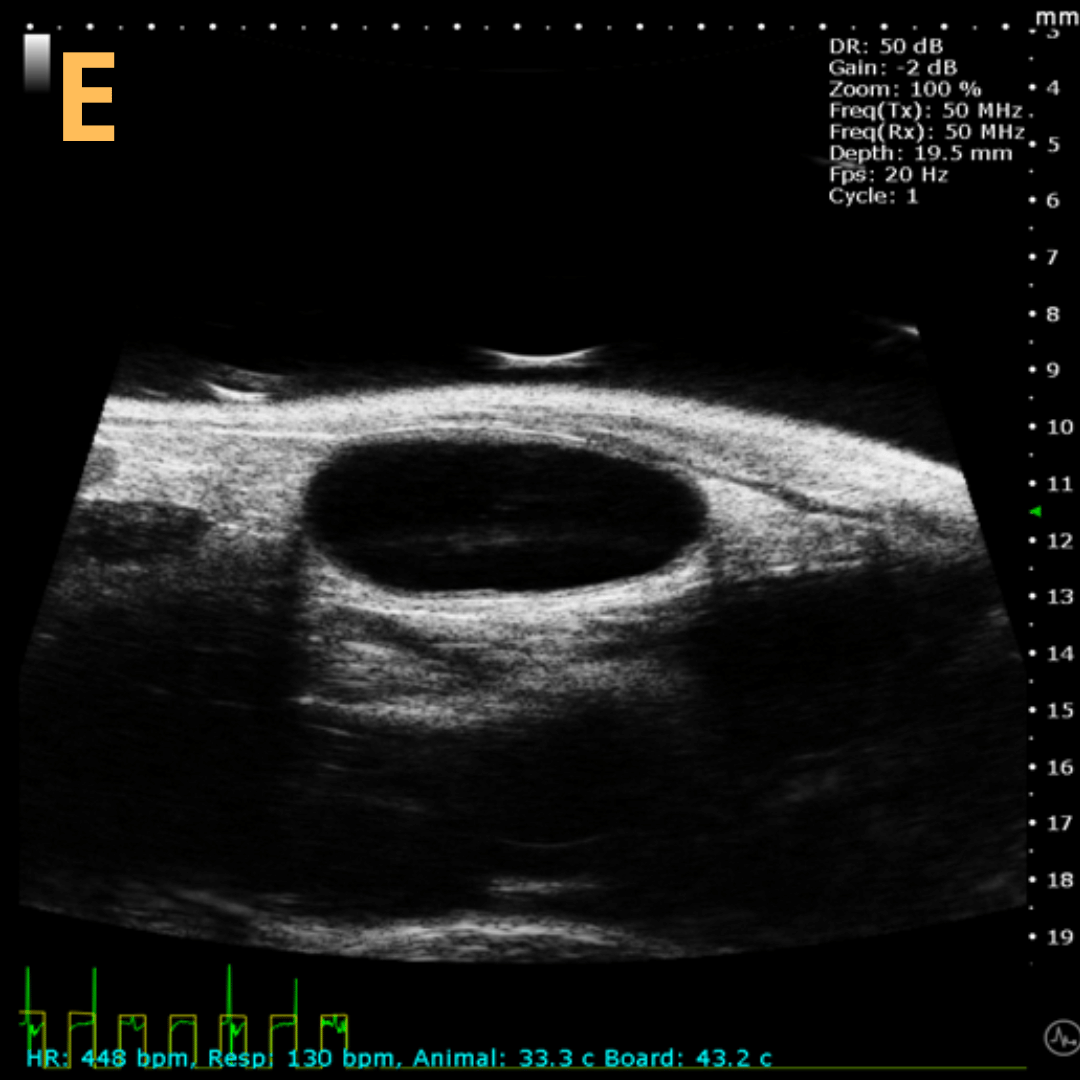

Basic Bladder Imaging

These are imaging from an emptied bladder (A – C) and a full bladder (D – F). This is A) a B-mode video scanning an emptied bladder with B) a still frame with C) the landmarks noted. This is D) a B-mode video scanning a full bladder with E) a still frame with F) the landmarks noted. Imaging on a wildtype C57B6J mouse model – acquired images are from Stephen Zderic’s lab at the Children’s Hospital of Philadelphia.

This is A) a B-mode video showing insertion of a thin-needle catheter via a larger-sized guide needle with B) the landmarks noted. C) is another example of this technique with D) the landmarks noted. E) Removal of catheter needle with F) the landmarks noted. Verification of successful injection via catheter is shown in G – H with G) showing the bladder before injection and H) showing after successful injection. Imaging on a wildtype C57B6J mouse model – acquired images are from Stephen Zderic’s lab at the Children’s Hospital of Philadelphia.